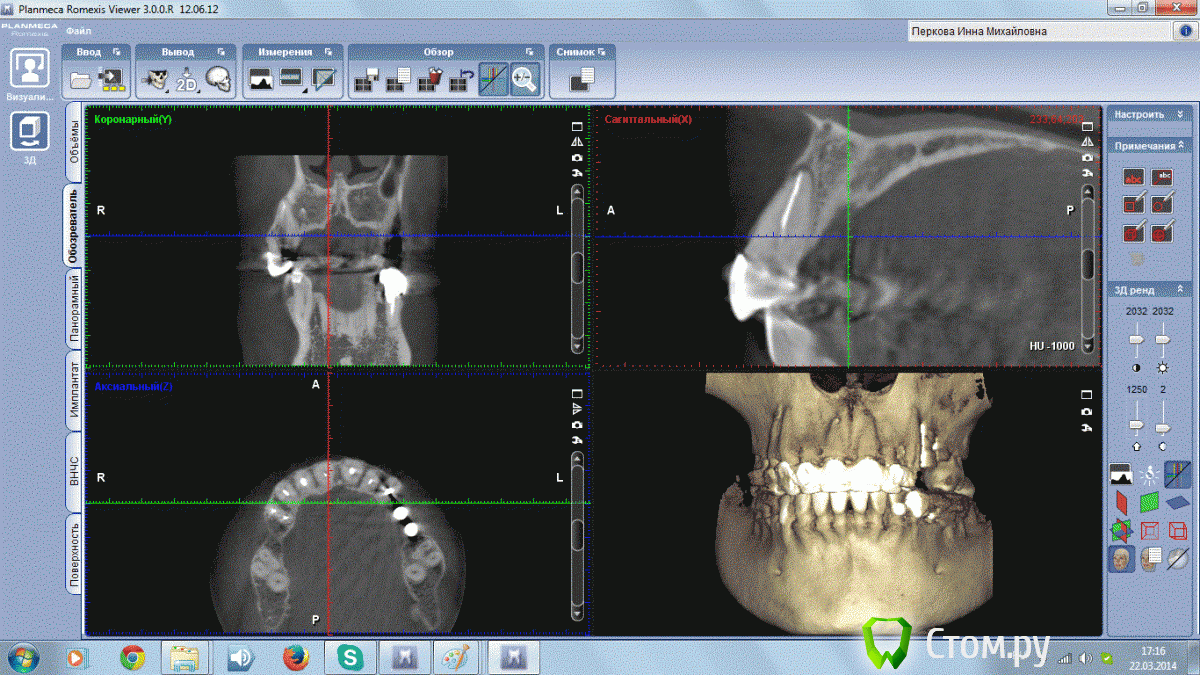

Инна Михайловна Опубликовано 22 марта, 2014 Поделиться Опубликовано 22 марта, 2014 (изменено) Добрый День!,У меня на 1 зубе обнаружили на КТ гранулему, но обнаружили уже после лечения канала. Долечен ли канал до верхушки? И посмотрите пожалуйста состояние остальных зубиков. Старая металлокерамика слетела, хочу делать новое протезирование. Изменено 22 марта, 2014 пользователем Инна Михайловна Ссылка на комментарий

Гарриевич Опубликовано 22 марта, 2014 Поделиться Опубликовано 22 марта, 2014 Пролечили зуб хорошо, до конца запломбировали. Все должно излечиться за полгода, год Ссылка на комментарий